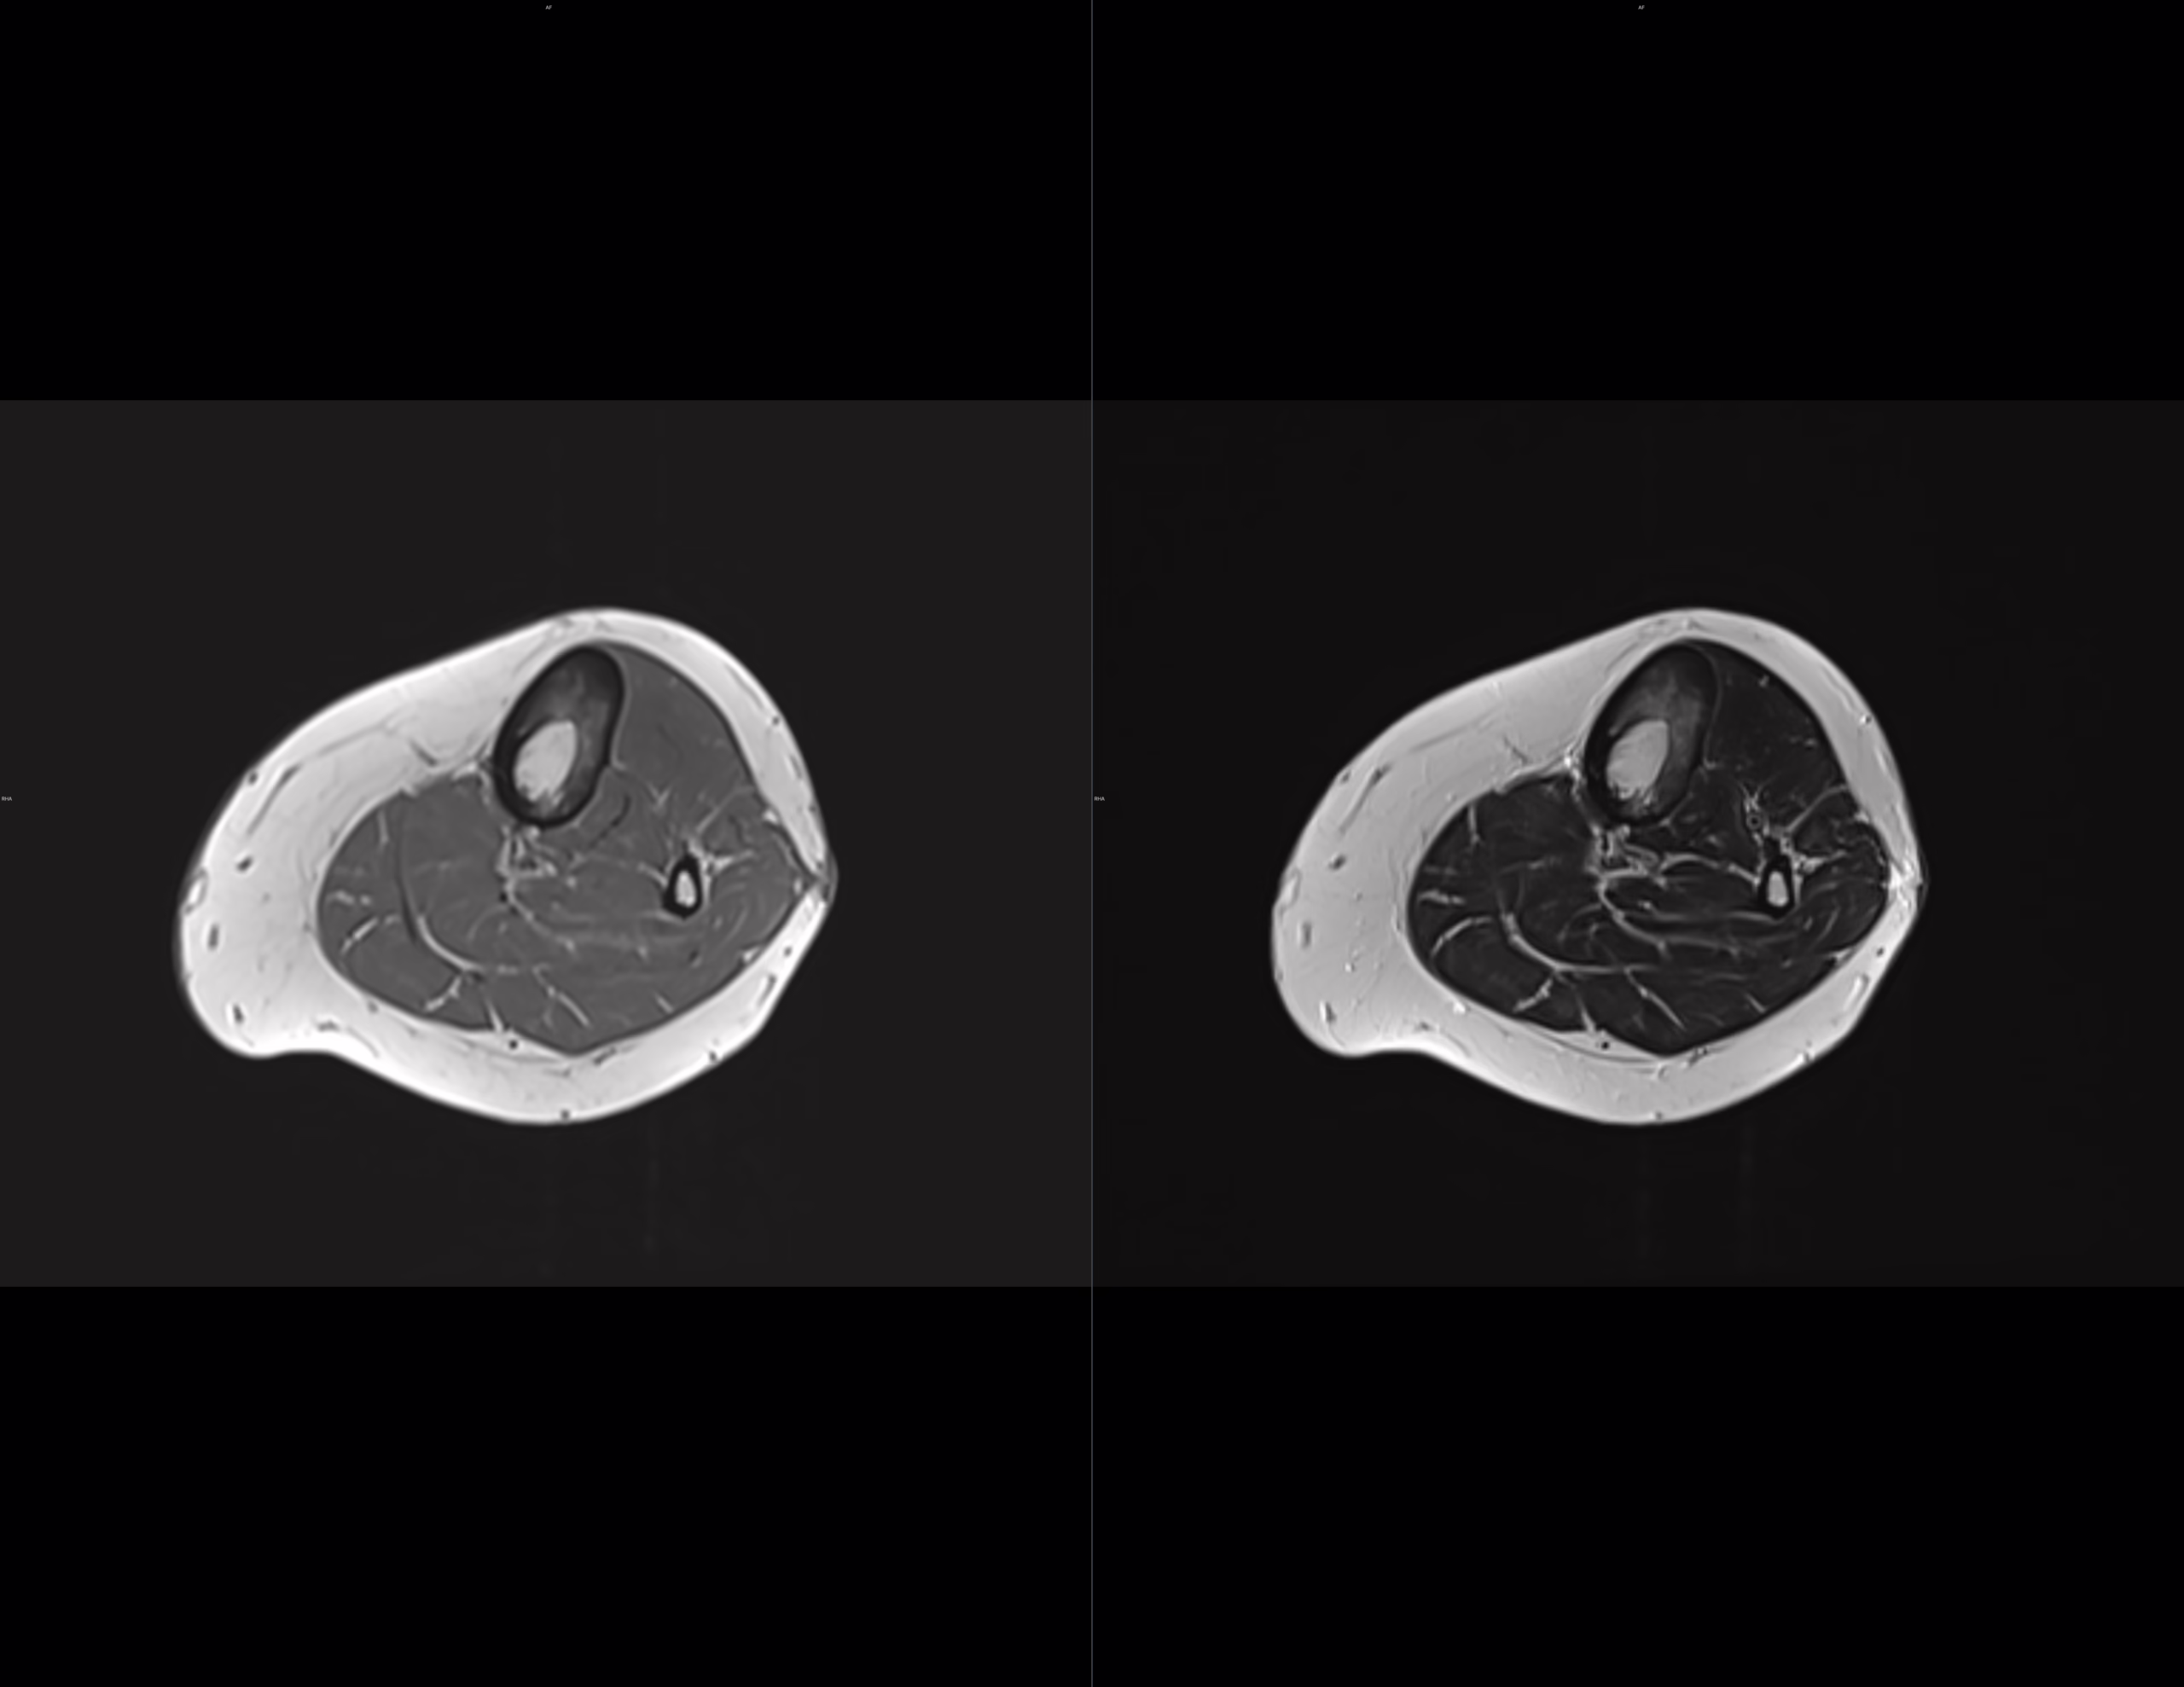

rnm

Se realizaron cortes sagitales, axiales y coronales con técnica de espín eco con el protocolo habitual.

Se identifican edema en el tejido celular subcutáneo adyacente a la tibia y grupos musculares en la región anterior y medial de la pierna.

Existen cambios en la morfología e intensidad del hueso esponjoso de la tibia que involucra la diáfisis proximal y tercio medio con áreas de baja intensidad en el hueso esponjoso medular así como de mayor intensidad, la cortical al parecer se encuentra conservada.

La intensidad de las estructuras musculares se encuentra conservada.

IMPRESION DIAGNOSTICA:

Edema en el tejido celular subcutáneo adyacente a la tibia y grupos musculares en la región anterior y medial de la pierna.

Existen cambios en la morfología e intensidad del hueso esponjoso de la tibia que involucra la diáfisis proximal y tercio medio con áreas de baja intensidad en el hueso esponjoso medular así como de mayor intensidad, la cortical al parecer se encuentra conservada, cambios de proceso infiltrativo óseo de etiología a determinar.